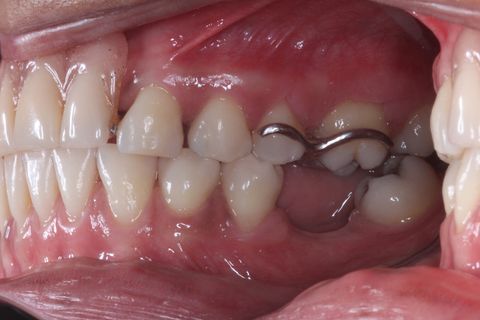

Foto Inicial. Paciente fazendo uso de Prótese Parcial removível.

Foto Perfil (uso de espelho). Lado esquerdo

Foto Perfil (uso de espelho). Lado Direito